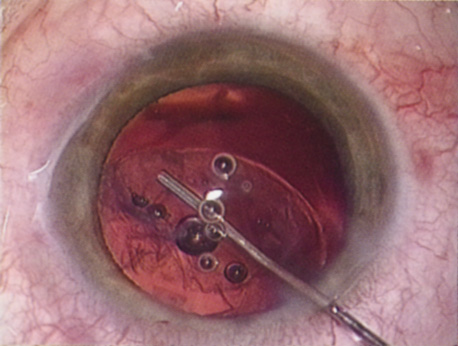

COMPROMISED ZONULES

The introduction of innovative adjunctive devices was able to improve the management of challenging cases. The capsular tension ring introduced independently by Tsutomu Hara37 and Toshiyuki Nagamoto38 in Japan was identified as a major weapon in managing zonular weakness by Ulrich Legler and Bernd Witschel of Germany.39 The CTR came to the United States in 1993,40 after which modifications by Robert Cionni,41 Iqbalk Ahmed and Alan Crandall,42 and Burkhard Dick were developed. Iris reconstruction had been primarily limited to suture techniques developed by Malcolm McCannel43 and later Steven Siepser.44 The prosthetic irides were introduced by German surgeons, Ranier Sundmacher45 and Volker Rasch,46 and brought to the United States by Kenneth Rosenthal and then Robert Osher in 1996.47 Although many devices had been developed to mechanically open the small pupil, it was the stretch technique developed by Luther Fry that greatly simplified these difficult cases.48 Improving visibility by staining the anterior capsule of the white cataract was introduced by Masayuki Horiguchi from Japan (ICG)49 and Gerritt RJ Melles from The Netherlands (Trypan Blue).50